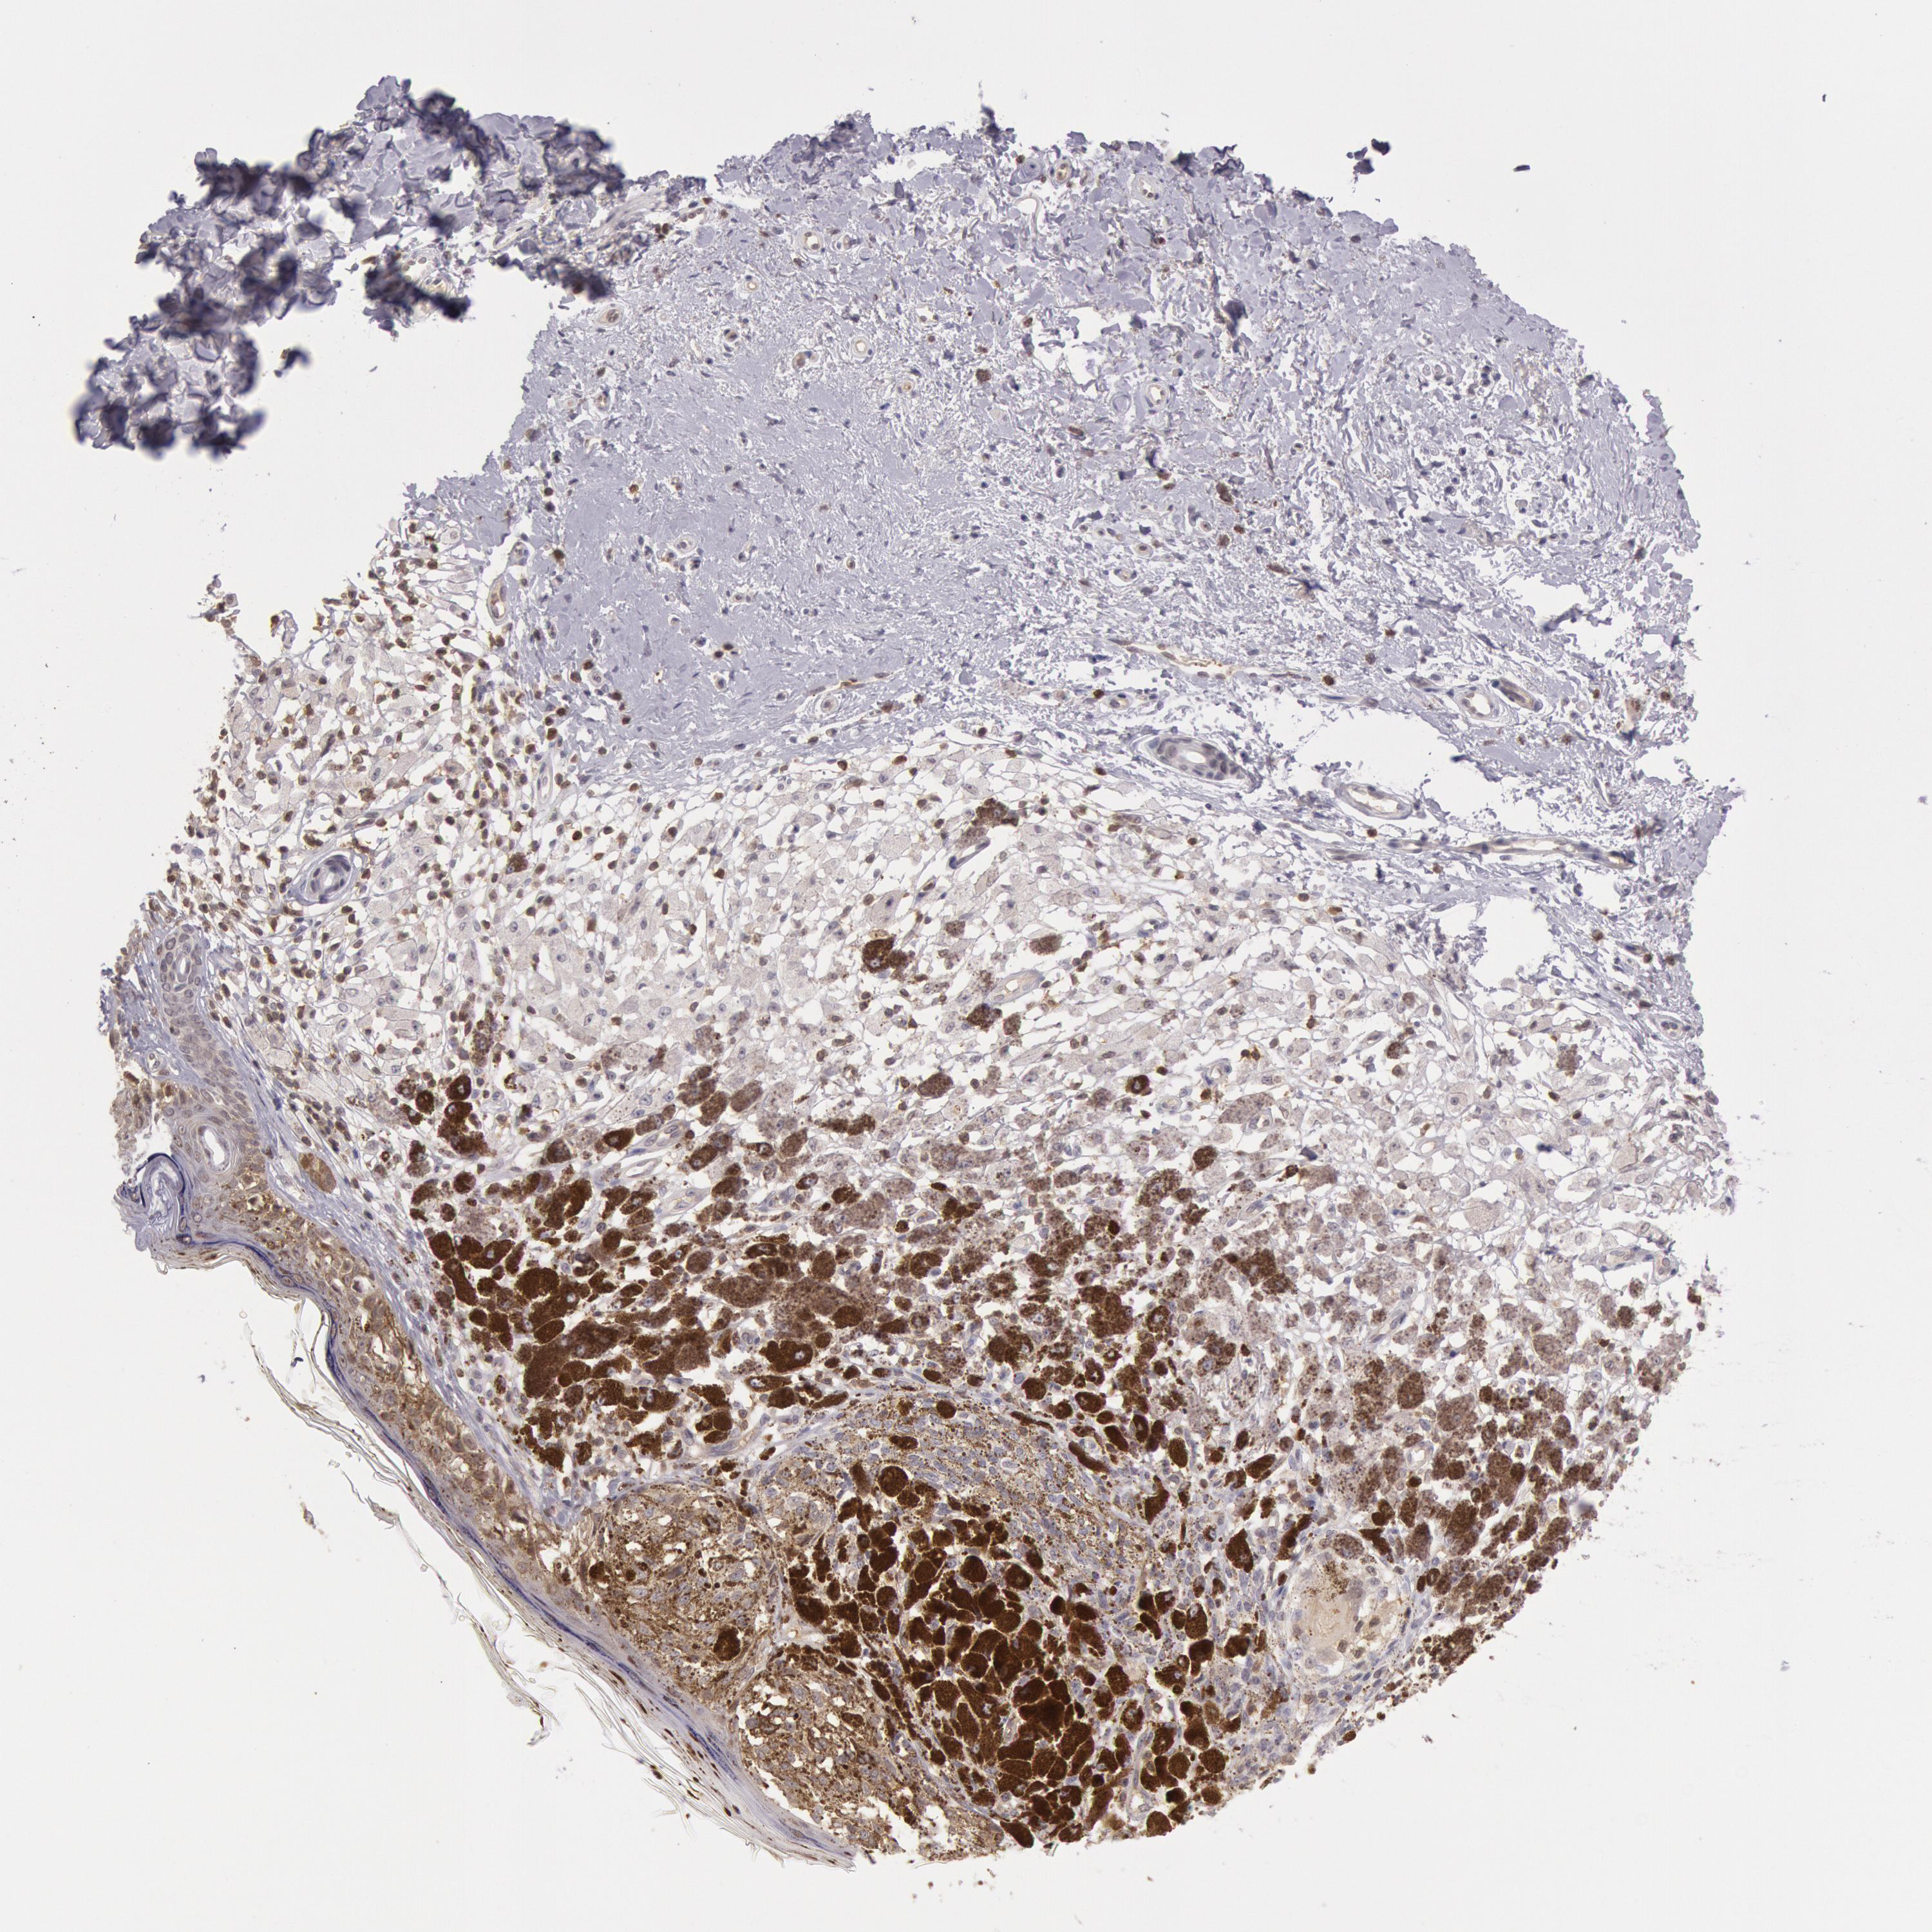

MELANOMA - Protein expressioni

A mouse-over function shows sample information and annotation data. Click on an image to view it in a full screen mode. Samples can be filtered based on level of antibody staining by selecting one or several of the following categories: high, medium, low and not detected. The assay and annotation is described here.

Note that samples used for immunohistochemistry by the Human Protein Atlas do not correspond to samples in the TCGA dataset.

Antibody stainingi

Antibody staining in the annotated cell types in the current human tissue is reported as not detected, low, medium, or high, based on conventional immunohistochemistry profiling in selected tissues. This score is based on the combination of the staining intensity and fraction of stained cells.

Each image is clickable and will lead to virtual microscopy that enables deeper exploration of all samples and also displays staining intensity scores, fraction scores and subcellular localization as well as patient and tissue information for each sample.

Antibody HPA001275

Antibody CAB017442

Staining

High

Medium

Low

Not detected

Intensity

Strong

Moderate

Weak

Negative

Quantity

>75%

75%-25%

<25%

None

Location

Nuclear

Cytoplasmic/membranous

Cytoplasmic/membranous,nuclear

Malignant melanoma, NOS

Malignant melanoma, Metastatic site